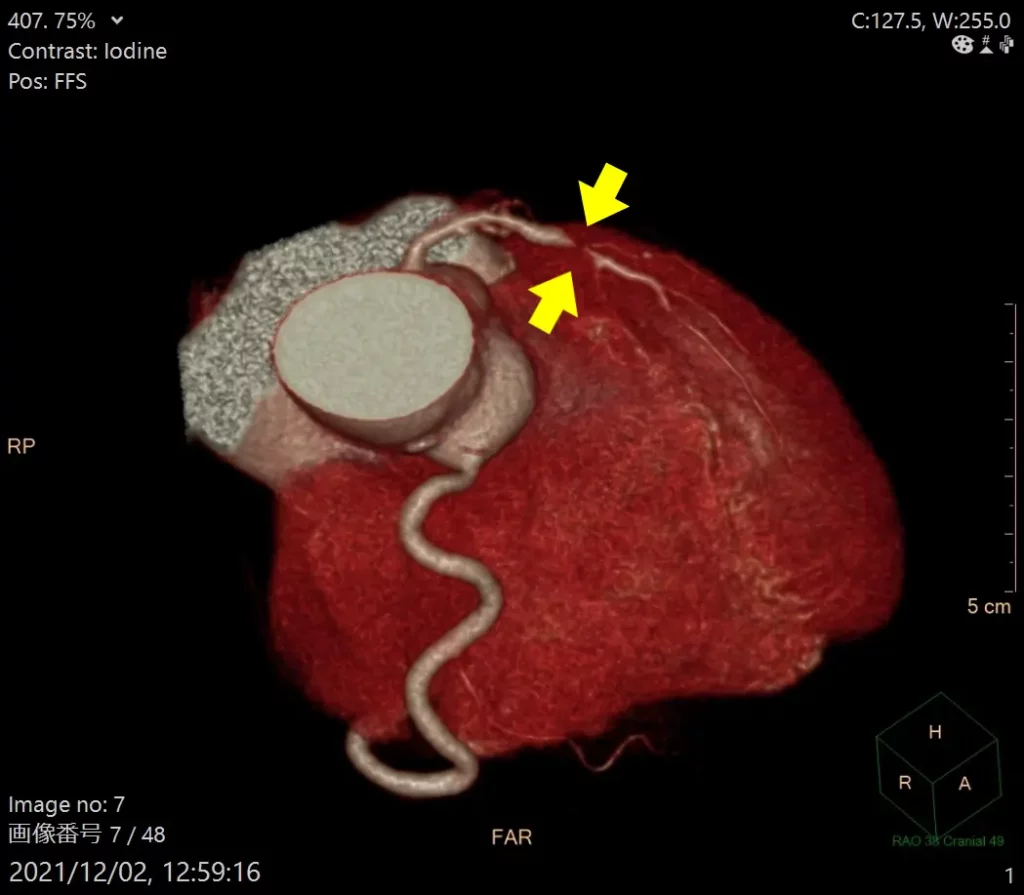

冠動脈CT検査(心臓CT検査)

造影剤を点滴したうえでCTで冠動脈を撮影します。血管の狭窄箇所(狭くなっている部分)や石灰化の有無を調べます。狭心症の検査では一番重要と言えます。比較的短時間で済み、体への負担が少ない検査です。ただし、造影剤にアレルギーがある方や腎機能が低下している方は注意が必要です。